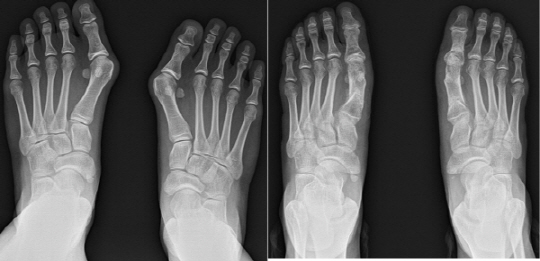

무지외반증은 엄지발가락 부위가 선/후천적 요인으로 돌출되는 질환이다. 변형은 한 번에 그치지 않고 시간이 지날 수록 그 정도가 심화된다. 발은 우리 몸 2% 남짓 작은 면적에 수백의 인대, 신경, 혈관조직이 분포되어 있다. 변형이 심화되면 이런 주변 조직손상을 피할 수 없고, 관절탈구, 보행불균형 탓에 족부 뿐 아니라 무릎, 고관절, 척추 합병증이 필연적으로 발생하게 된다. 때문에 전 세계적으로 변형각도가 15도 이상이 중등도 단계에서부터 빠른 치료가 요구되는 것이다.

이호진, 배의정 원장은 "교정술은 뼈를 깎아 정렬을 맞추지 않는다. 돌출 부위에 실금을 낸 후 내측으로 당겨 정렬을 맞춘 후 정렬이 틀어지지 않도록 일정기간 핀으로 고정하는 방식이다. 평균 20분 내외 짧은 수술시간과 술식의 변화와 수술 부위에 통증을 최소화하는 복합약물주사 투여로 통증이 크게 경감되어 빠른 회복과 양측 무지외반증 동시교정이 가능하다"고 설명했다.

실제 이들이 발표한 SCI 논문에서 교정술 및 복합약물주사 투여 환자 VAS SCORE는 평균 2점으로 기존 술식보다 무려 3.5배의 통증경감 효과와 평균 입원기간도 불과 2일로 5배 가량 빠른 회복과 술 후 사고/부상 등 외상요인을 포함해도 합병증 발생률은 1%미만의 높은 수술성공율을 보이며 교정술 도입이 치료부담 개선에 큰 도움이 됨을 확인할 수 있었다.